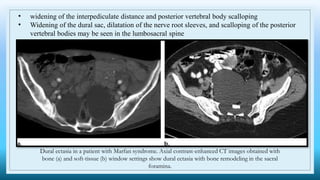

• widening of the interpediculate distance and posterior vertebral body scalloping

• Widening of the dural sac, dilatation of the nerve root sleeves, and scalloping of the posterior

vertebral bodies may be seen in the lumbosacral spine

Dural ectasia in a patient with Marfan syndrome. Axial contrast-enhanced CT images obtained with

bone (a) and soft-tissue (b) window settings show dural ectasia with bone remodeling in the sacral

foramina.